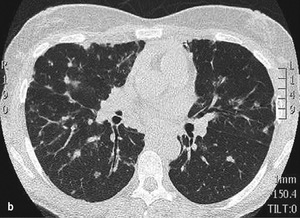

Rycina. (a) Zdjęcie RTG klatki piersiowej wykonane u 26-letniej kobiety z powodu suchego kaszlu wykazuje obustronne powiększenie węzłów chłonnych wnęk i okołownękowe miąższowe zmiany guzkowe. (b) Tomografia komputerowa lepiej uwidocznia guzki miąższowe rozmieszczone wokół naczyń limfatycznych oraz cechy zapalenia ziarniniakowego.